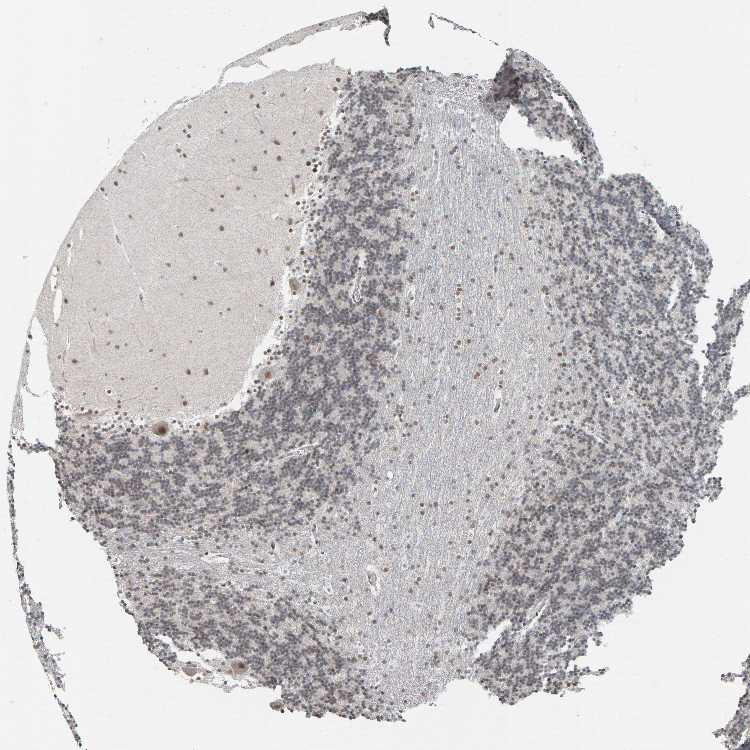

CEREBELLUM - Antibody stainingi

Antibody staining in the annotated cell types in the current human tissue is reported as not detected, low, medium, or high, based on conventional immunohistochemistry profiling in selected tissues. This score is based on the combination of the staining intensity and fraction of stained cells.

Each image is clickable and will lead to virtual microscopy that enables deeper exploration of all samples and also displays staining intensity scores, fraction scores and subcellular localization as well as patient and tissue information for each sample.

Antibody HPA016578Antibody HPA023505

Purkinje cells HighMedium

Cells in granular layer Not detectedNot detected

Cells in molecular layer HighLow